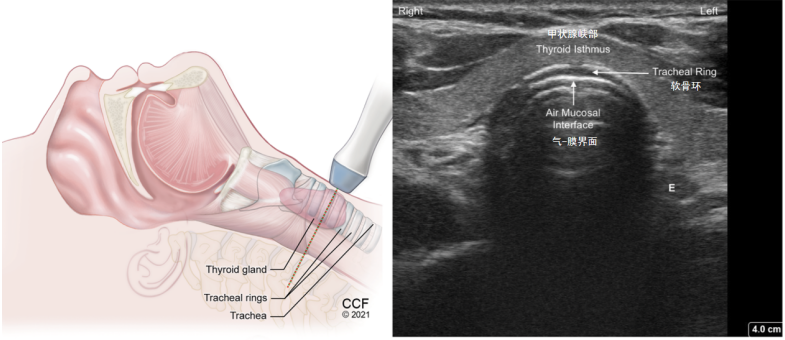

(5)气管软骨环横切面(图13):探头再往下就看到一个等回声或低回声结构,即为甲状腺的峡部,在进行气管切开操作时,需要进行定位,以免出现误穿和损伤。

图片

图13  气管软骨环横切面